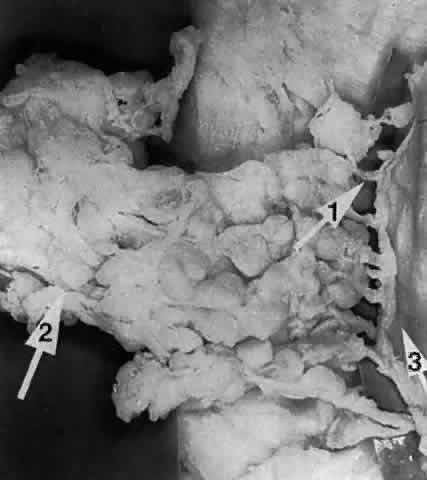

Sanderson and Stasior4 found islands of “peripheral” lacrimal glandular tissue below the lateral canthus unassociated with the main gland in 60% of cadaver specimens (Fig. 8). These peripheral islands of glandular tissue were found less commonly in or above the lateral canthal tendon.

Fig. 8. “Peripheral” lacrimal gland lobules (arrow 1) are seen below the right lateral canthus (arrow 2) and separate from the palpebral lobe of the lacrimal gland (arrow 3). (Courtesy of James Sanderson, MD, Orkan Stasior, MD, and George Stasior, MD)